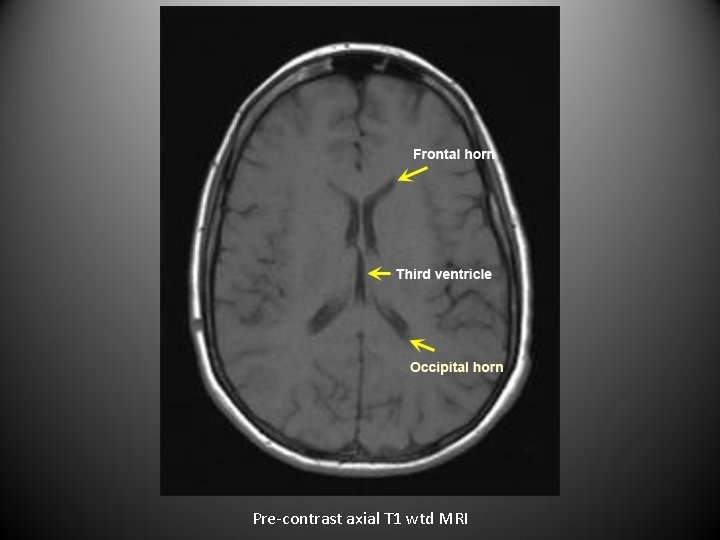

• For axial images you need to know the level. • The next set of images are axial sections of brain from top to bottom.

Pre-contrast axial T 1 wtd MRI